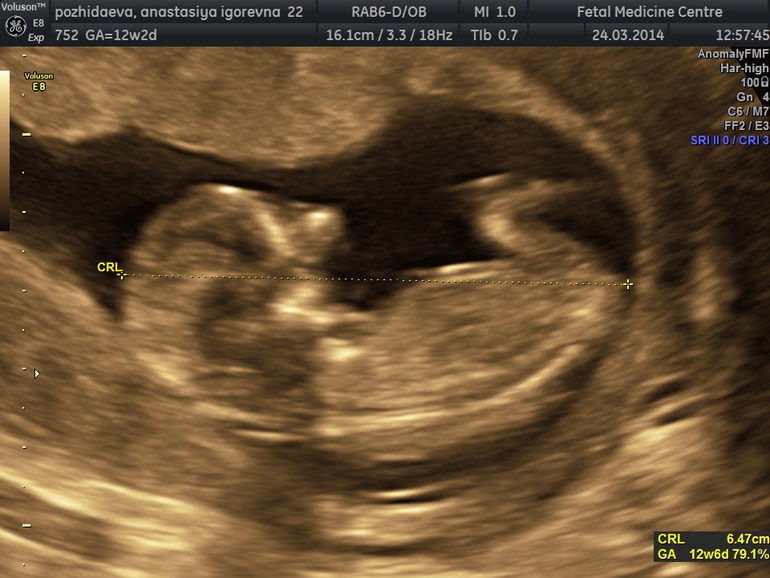

Забыла сообщить самое главное, мы были на скриннинге, все у нас ттт хорошо, нам предположили мальчика, посмотрим на следующем узи, так интересно, наше чудо впервые познакомилось с папой и был этому очень рад, махал ручками и ножками, чудо наше и солнышко, вообщем у них это взаимно)

Вот он-наш птенчик)

На приеме у врача нас похвалили и сказали, что мы хорошо растем по нормам.